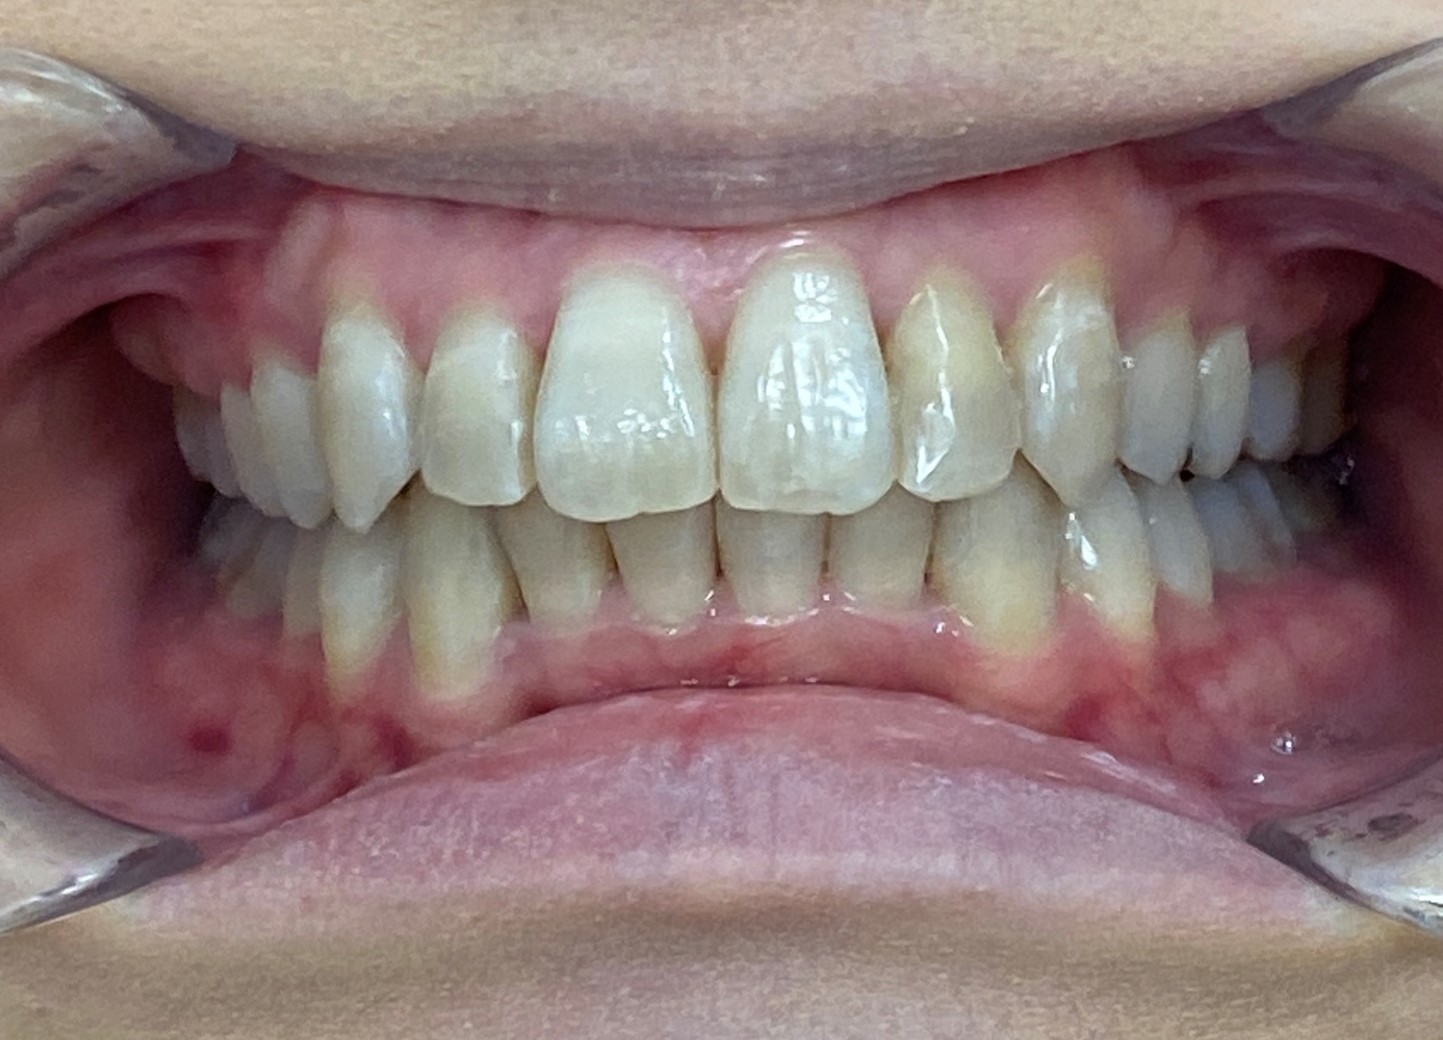

上下とも歯がまっすぐに並び、美しい口元になりました。

患者様にも「自信をもって笑えるようになった」と大変お喜びいただけました。

現在は、歯並びの後戻りを防止するための「保定装置」をご使用いただきながら経過を観察しています。